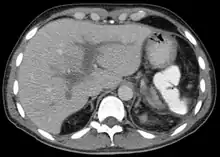

Thrombose portale sur une coupe de scanner.

L'image de thrombose de la veine porte peut être obtenue avec une échographie abdominale, ou plus facilement par une scanner ou une IRM.